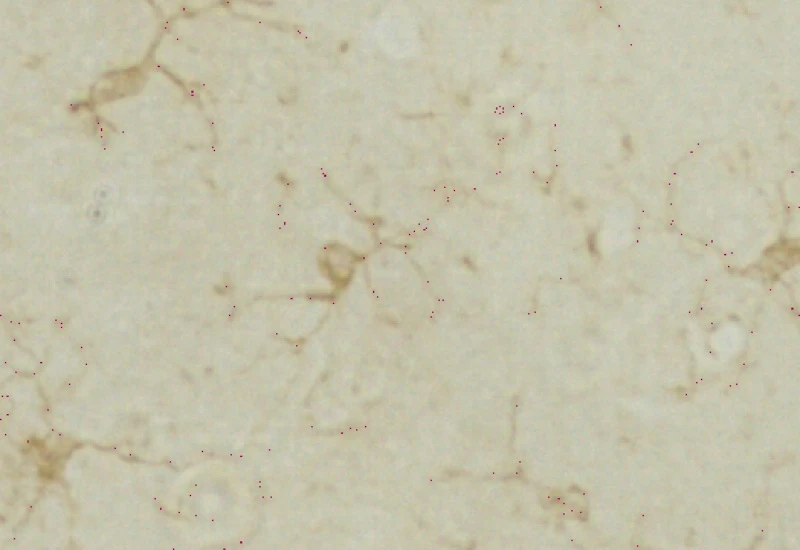

The IHC Microglia App detects microglia soma based on a specifc staining and further identifies branches as well as primary and secondary branching points. It outputs number and area of cells, number of primary and secondary branching points as well as area and lenght of the detected branches.

Microglia detection